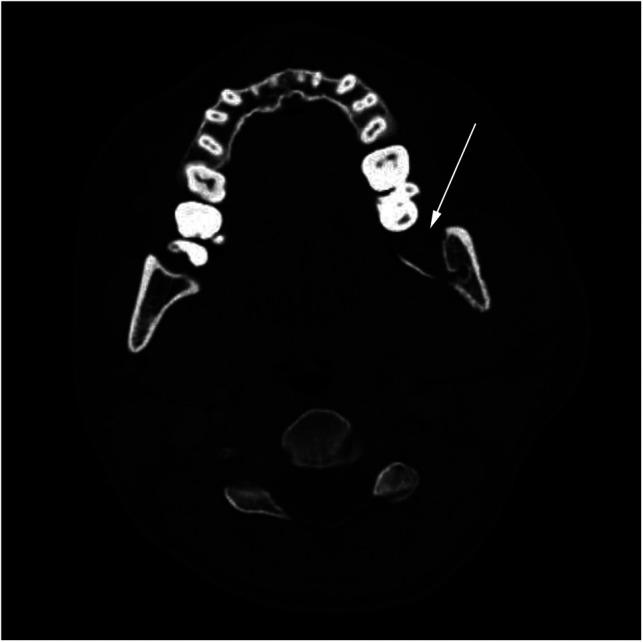

Osteomyelitis of the jaw is an uncommon infection that arises from the flora of the oral cavity or sinuses and affects immunocompromised and polymorbid patients. Treatment includes surgical debridement and long regiments of broad-spectrum antibiotics. We present three cases of complicated jaw osteomyelitis presented with concurrent COVID-19 infection, including only two reported cases of odontogenic COVID-related osteomyelitis. The two mandibular cases were patients in their 30s with no comorbidities. The first case was an asymptomatic COVID-19-positive patient who developed an odontogenic infection after tooth extraction that was complicated by the second bout of abscess formation and localized osteomyelitis. The second case was a COVID-19-positive patient with an odontogenic infection that presented as airway compromise due to trismus and neck edema, which required an emergency tracheotomy. He developed osteomyelitis of the mandibular ramus that was reconstructed with a titanium plate. The third case was a polymorbid post-COVID-19 patient who developed a protracted infection of the maxillary sinus that resulted in the loss of an eye, destruction of the maxilla, palate, and parts of nasal cavum, and oronasal incontinence. The defect was reconstructed with a microvascular anterolateral thigh flap. We hypothesize that COVID-19-related immune dysfunction and microvascular changes contributed to osteomyelitis in our patients.

颌骨骨髓炎是一种罕见的感染性疾病,由口腔或鼻窦菌群引起,影响免疫功能低下和患有多种疾病的患者。治疗方法包括手术清创和长期使用广谱抗生素。我们报告了三例并发COVID-19感染的复杂性颌骨骨髓炎病例,其中仅两例为牙源性COVID相关骨髓炎。两例下颌骨病例为30多岁无合并症的患者。第一例是一名无症状的COVID-19阳性患者,拔牙后发生牙源性感染,并发第二次脓肿形成和局限性骨髓炎。第二例是一名COVID-19阳性患者,患有牙源性感染,因牙关紧闭和颈部水肿导致气道受压,需要紧急气管切开术。他发生了下颌支骨髓炎,并用钛板进行了重建。第三例是一名COVID-19后的多病患者,上颌窦发生了迁延性感染,导致失明、上颌骨、腭部和部分鼻腔破坏以及口鼻失禁。缺损用股前外侧游离皮瓣进行了重建。我们推测,COVID-19相关的免疫功能障碍和微血管变化导致了我们患者的骨髓炎。